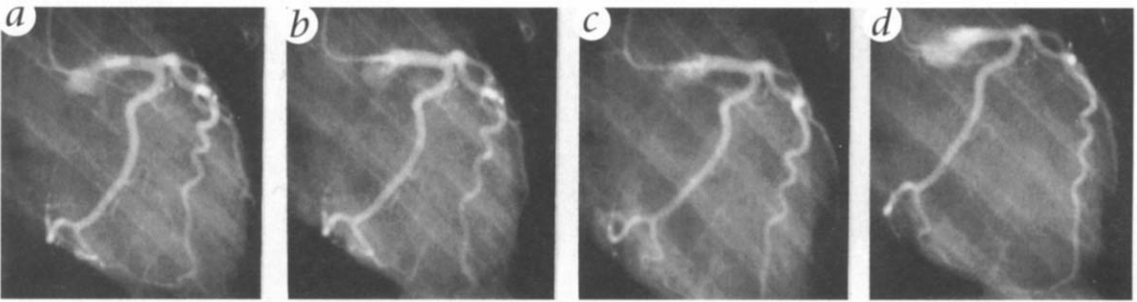

MPA group monkeys were not protected against vasospasm, as shown in Fig. 2 and Tables 1 and 2. Although there was also apparently normal dilator function, as shown by a low dose of ACh (Fig. 2, a and b), the S+U protocol resulted in segmental occlusion and vasospasm (Fig. 2c). This strong (92%) constriction, including at least one hour-glass pattern, was sustained for 15 minutes, even longer than our criterion for vasospasm. After 15 minutes, IC mibefradil was injected to relieve the vasospasm and restore cardiac performance in one animal (Fig. 2d). Blood pressure, which reached a nadir of 38/20 mm Hg in this monkey returned to 124/84 mm Hg after mibefradil administration.

Figure 2. Coronary angiograms of an E2 + MPA treated monkey show the control artery diameters (a), dilation with low dose (1 μm) ACh (6), vasospasm 15 min after the first injection of 100 μm serotonin + 1 μm U46619 (c)and vasodilation with mibefradil 15 min after a subsequent vasospasm (d). The time elapsed between c and d is 33 min. Thus, MPA + E2 eliminated the E2 protection against vasospasm, as shown in c and all MPA treated monkeys (Table 1).